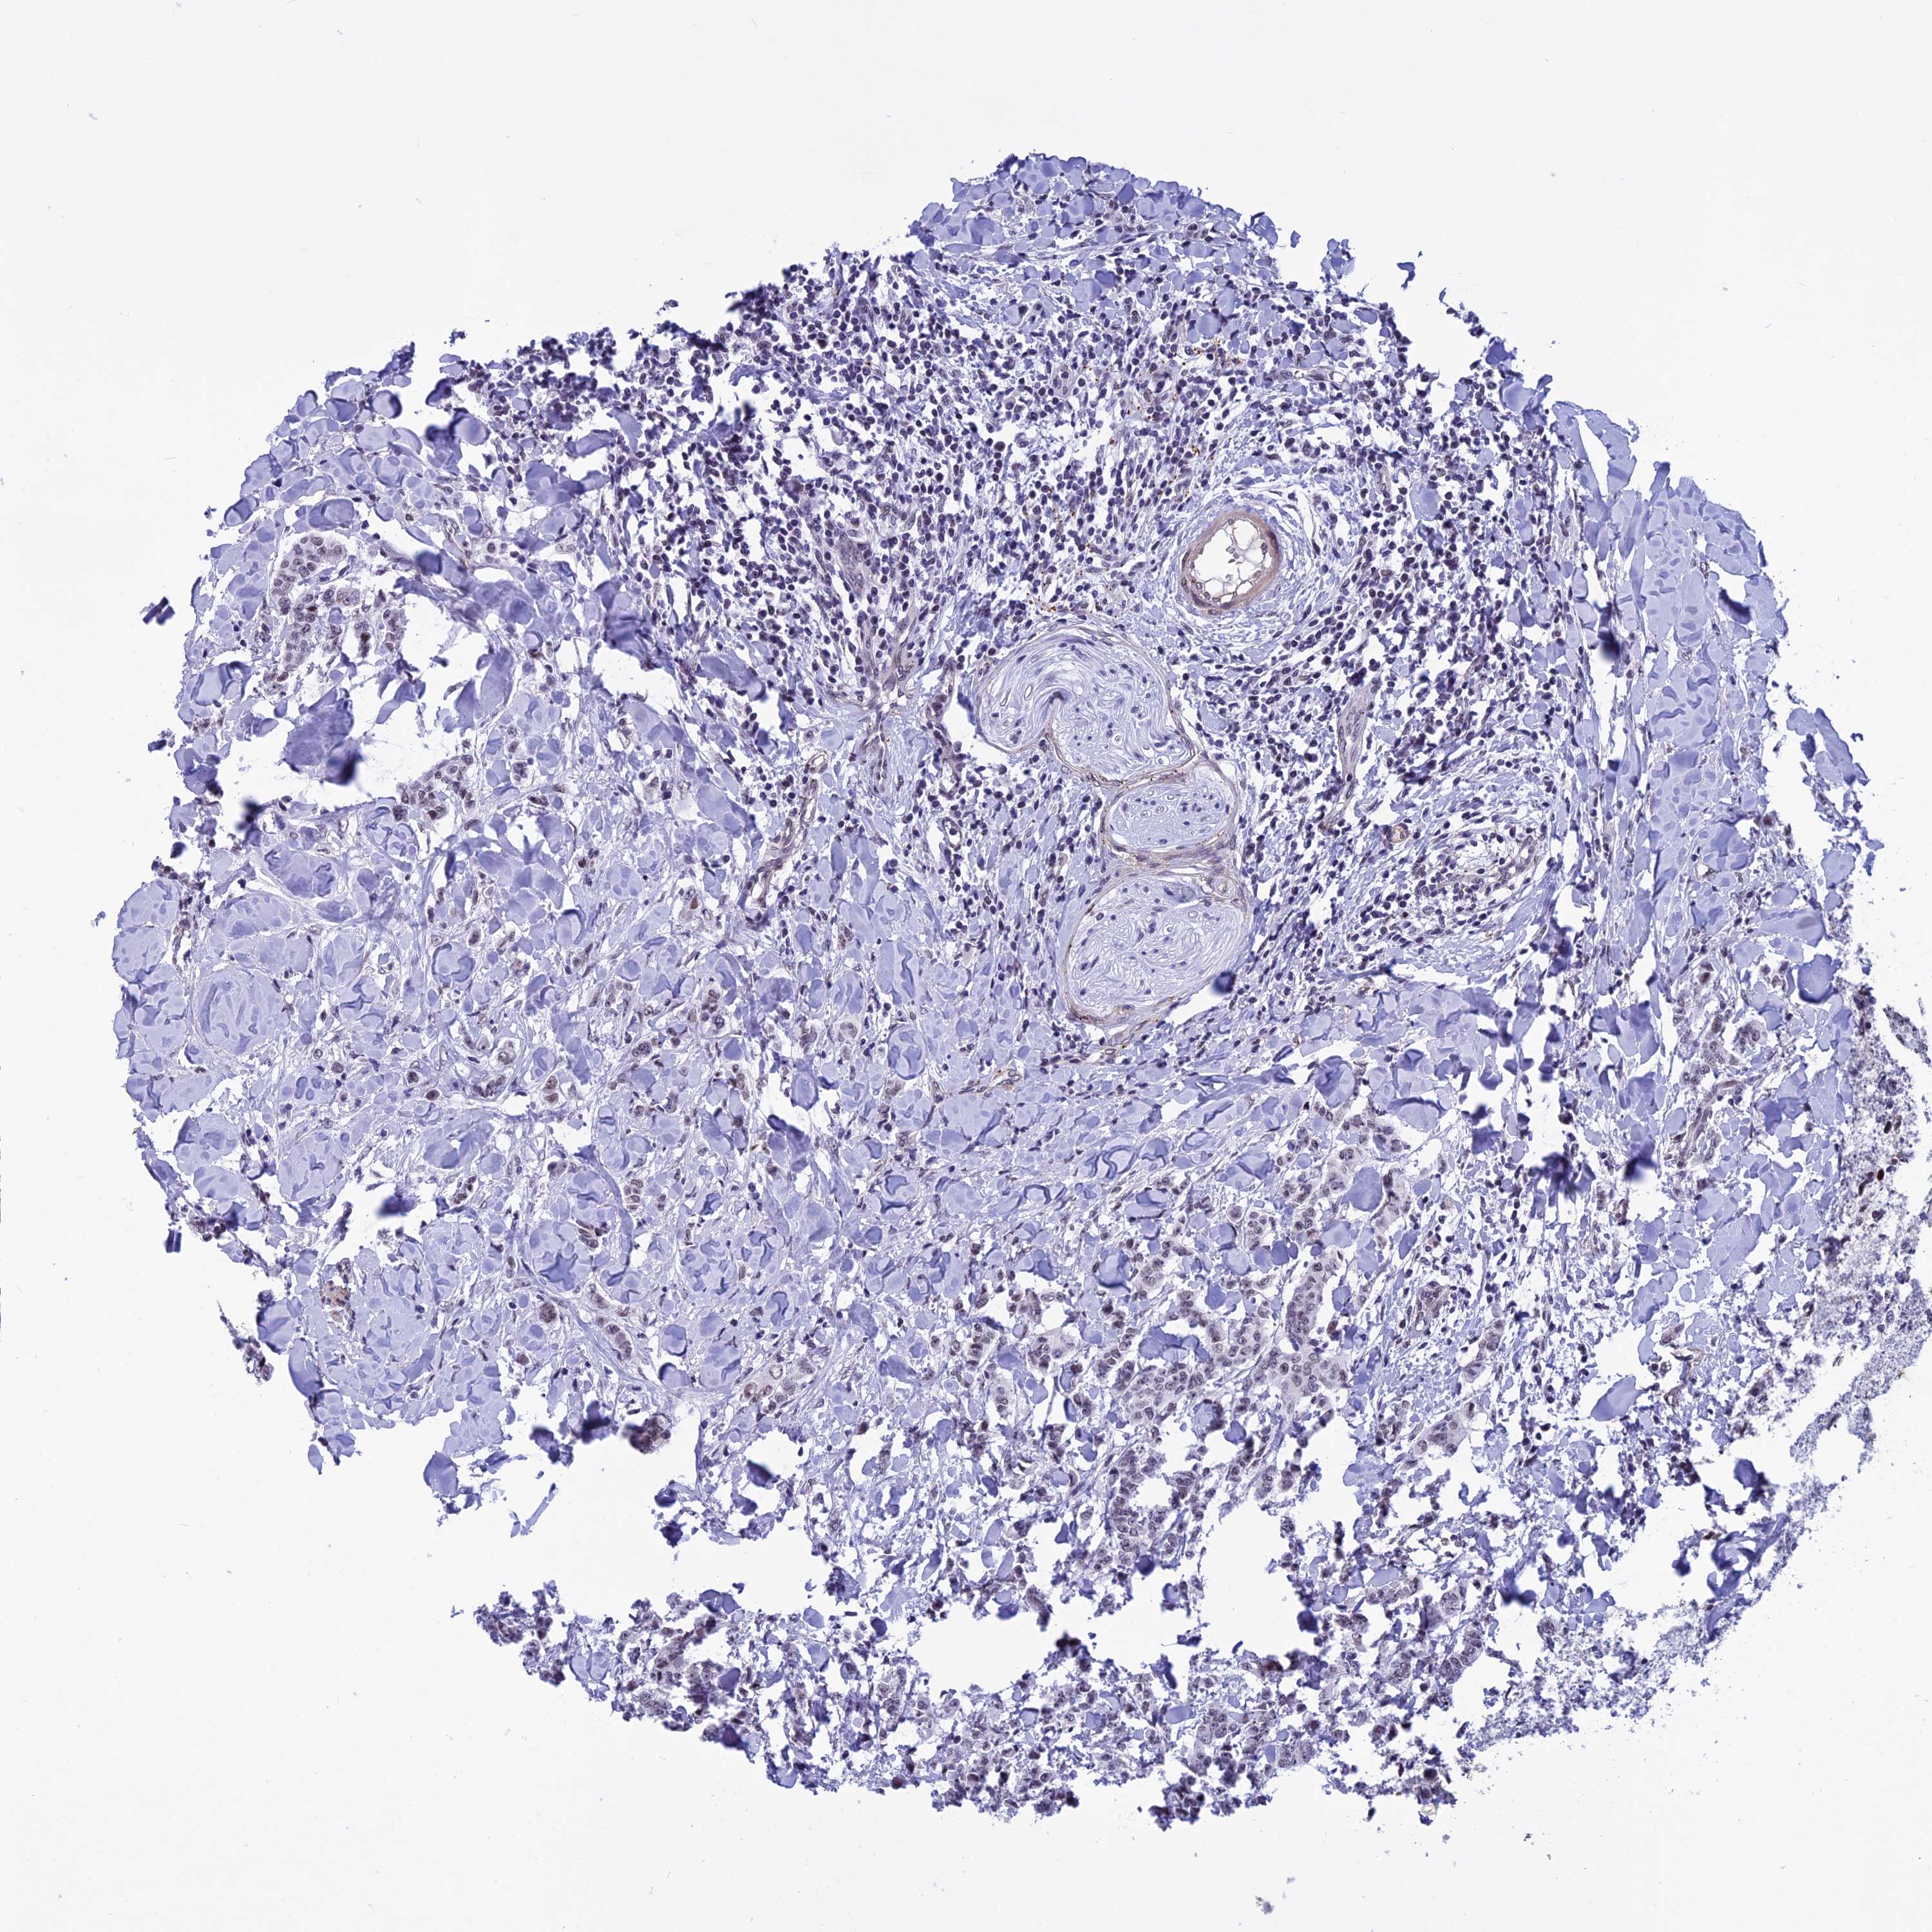

CANCER BREAST CANCER Show tissue menu

BRCA TCGA BRCA VALIDATION PROTEIN EXPRESSION